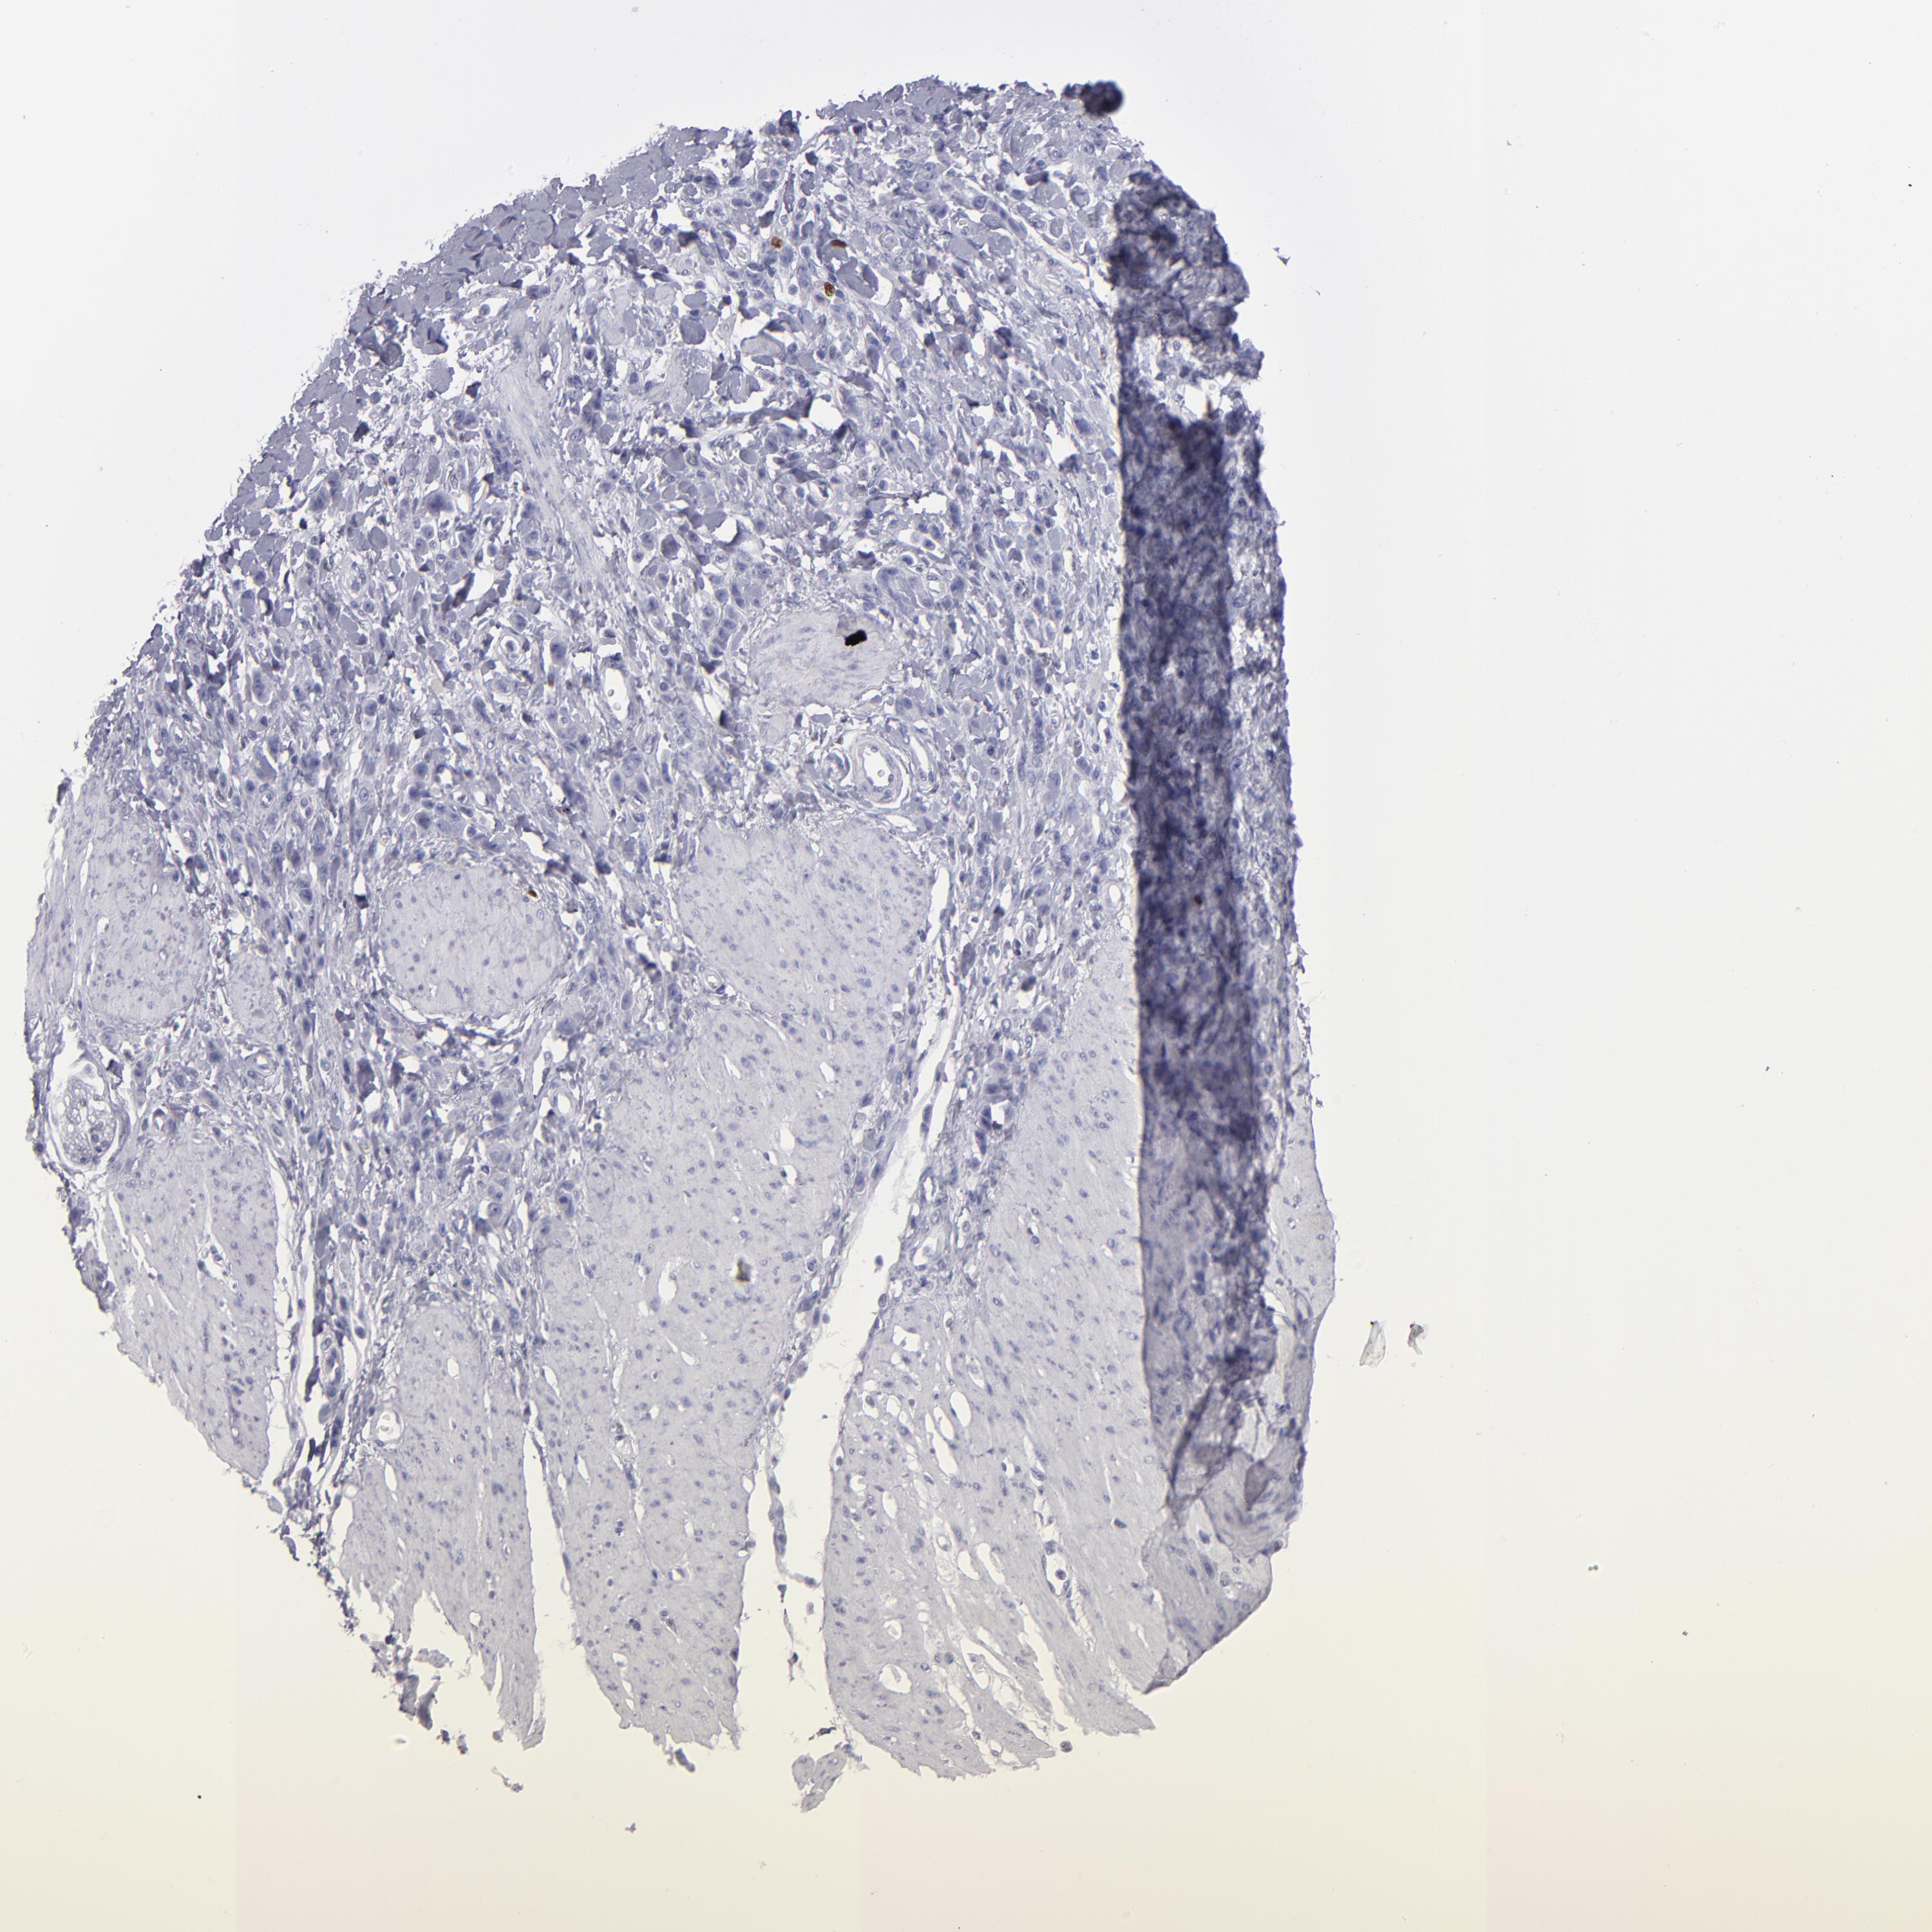

STOMACH CANCER - Protein expressioni

A mouse-over function shows sample information and annotation data. Click on an image to view it in a full screen mode. Samples can be filtered based on level of antibody staining by selecting one or several of the following categories: high, medium, low and not detected. The assay and annotation is described here.

Antibody stainingi

Antibody staining in the annotated cell types in the current human tissue is reported as not detected, low, medium, or high, based on conventional immunohistochemistry profiling in selected tissues. This score is based on the combination of the staining intensity and fraction of stained cells.

Each image is clickable and will lead to virtual microscopy that enables deeper exploration of all samples and also displays staining intensity scores, fraction scores and subcellular localization as well as patient and tissue information for each sample.

Antibody HPA002267

Antibody HPA002531

Antibody CAB013480

Staining

High

Medium

Low

Not detected

Intensity

Strong

Moderate

Weak

Negative

Quantity

>75%

75%-25%

<25%

None

Location

Nuclear

Cytoplasmic/membranous

Cytoplasmic/membranous,nuclear

Adenocarcinoma, NOS

Adenocarcinoma, High grade